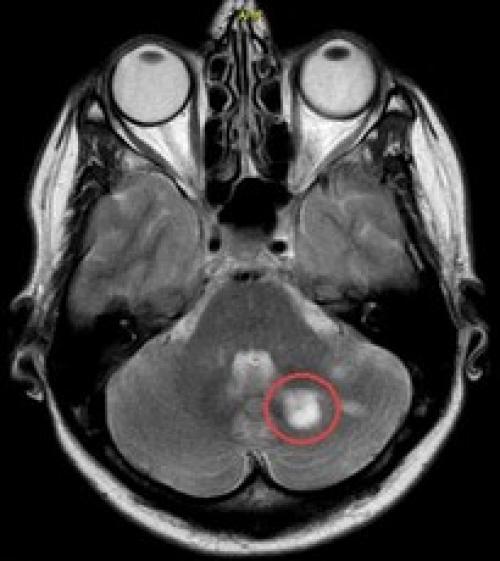

зуба, кружком обведен | Стреляющая боль во всех трех ветвях была следствием плохого кровообращения в мозговых отделах тройничного нерва у пожилой женщины. Кружком обведен участок мозга, пострадавший от закупорки одного из сосудов головного мозга. Проверить сосуды головы и шеи | Невралгия тройничного нерва была у молодой женщины из-за давления одной из мозговых артерий на корешок тройничного нерва. На МР-томограмме видно пересечение тройничного нерва (идет вертикально) с артерией (идет горизонтально). Артерия оказывала давление на тройничный нерв в месте его выхода из ствола мозга. |

- Сдавливание (компрессия) . Происходит, когда на нерв оказывается давление извне. Часто причиной явления служит контакт кровеносного сосуда (артерии или вены) с корешком тройничного нерва. Реже такое случается при опухолях, кистах или других образованиях.

- Воспаление . Инфекции, такие как вирус простого герпеса, могут вызывать воспаление тройничного нерва. Также воспаление возможно в результате аутоиммунных или других патологических состояний. Воспаленный нерв становится чувствительным, что проявляется сильными болями и другими неприятными симптомами. Воспаление может носить как острый характер, так и переходить в хроническую форму, требующую продолжительного лечения.